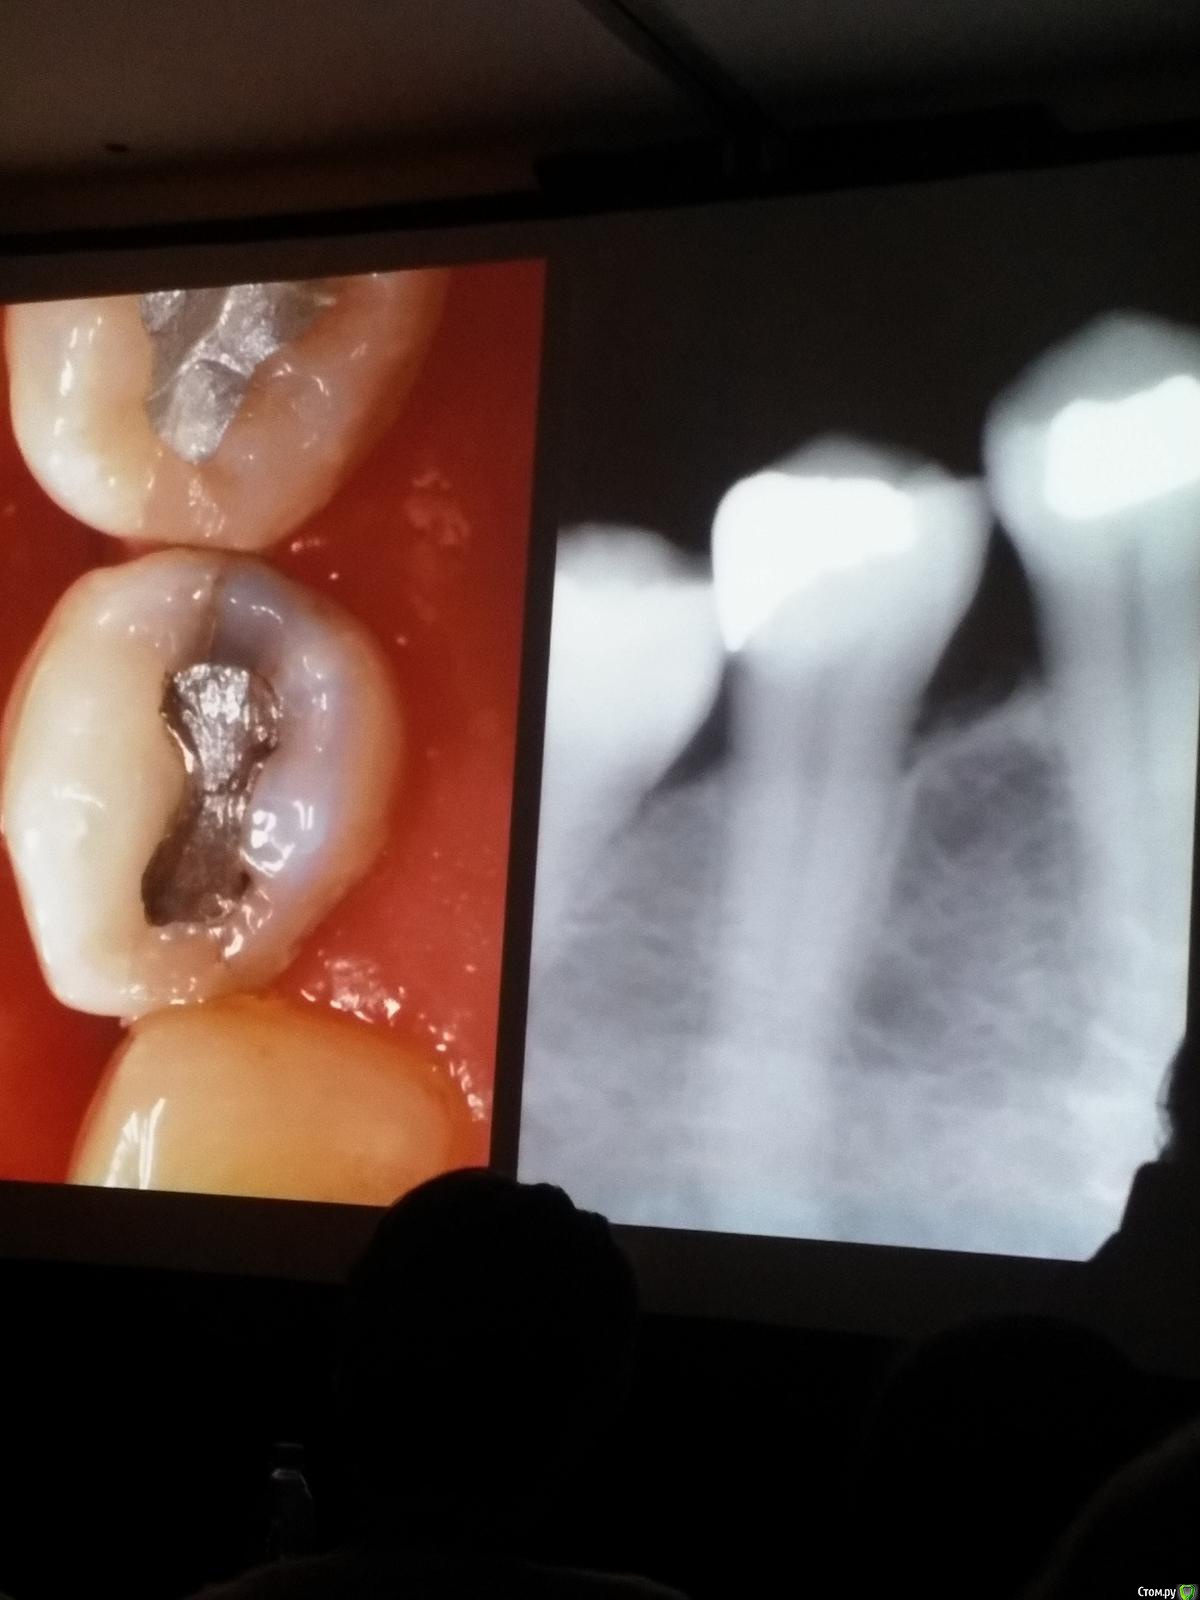

Популярный пост Kolchanov Опубликовано 11 марта, 2017 Популярный пост Поделиться Опубликовано 11 марта, 2017 (изменено) Товарищи, скажу я вам...........Вкратце. Может я где-то что-то и приврал, надеюсь, кто еще был, поправят. Честно говоря немного прибалдел от уровня Доктора. Очень, очень высоко! Приедет еще раз, пойду еще. 1) Фиссуры зондирует острым зондом и выпиливает все дотла. По факту у него уже пломбы, а не герметизация.2) Bite-wing у первичных пациентов всегда.3) Если кариес диагносцирован, то лечить его, пофиг какой он там. Эмали, дентина…4) Препарирует до твердого (или до вскрытия J ). CAD, СID… в топку. Кариес маркером не пользуется, проверяет острым зондом/экскаватором. Вычищает все дотла. Считает, что даже небольшое количество бактерий в дентине под пломбой вызывают хроническое воспаление в пульпе. С его слов у него на контроле где-то 500 вскрытий, не удивительно при таком подходе к очистке.5) Тщательная изоляция. Коффер порвался – меняет. Большое значение герметичности реставрации. под замену6) Критерии обратимости и необратимости.Гистологически, обратимый тот, что без абсцессов в пульпе, но клинически это понять нельзя, только предположить.Здесь был бы обратимый, если бы не удалил. Нет микробов в пульпе. Линия - граница обработки.Покрытие 27 лет назад. Dycal, СИЦ, композит. От дайкала одно воспоминание.7) Вскрылись. Размер перфорации, возраст и прочее не играют роли, важно только состояние пульпы, т.е. диагноз.Примеры перфораций.8) Кровотечение останавливает стерильным ватным шариком. Если останавливается, то покрытие, если нет, то пульпотомия или пульпэктомия.9) Использует гидроокись кальция (порошок), перекрывает Dycal или СИЦ. Потом восстановление Нередко под IRM, потом все убирает (через пару-тройку месяцев) и смотрит, что получилось. Порой приходится повторять! Использует и МТА, его тоже убирает.10) Наблюдение 6мес, 1 год, 2…. Все может провалиться и через месяц и через 24 года.Примеры проваловНиже - 24 года спустя появилась дуля. 11) Неравномерная облитерация полости зуба на RG (после покрытия) – признак текущего хронического воспаления, где-то остались микробы. Рекомендует эндо.12) Мостик который образуется – это не дентин! И одонтобласты не регенерируют и новые не образуются. Что это такое он и сам не знает, но раз это твердые ткани, то и наплевать.Вот фиолетовое это дентинные опилки вмурованные в розовую ткань бог знает кем сформированную.13) Пульпотомия в зубах с несформированной верхушкой и в сформированных, при подозрении на частичное поражение коронковой пульпы. Иссекается стерильным алмазным бором часть пульпы, гидроокись, временная пломба на 90 дней, после повторное раскрытие, оценка результата, восстановление в случае формирования твердых тканей. Гипохлоритом можно мыть, можно не мыть, если мыть, то 0,5-1%.14) В апикальной части пульпа чаще витальна, чем нет.15) Периапикальные поражения возникают по причине поступления токсинов микробов с током крови, а не самих бактерий.16) За апикальные расширения в полностью некротических случаях. Надо механически отодрать биопленку и срезать инфицированный дентин. На ирриганты надежды мало.17) Биопленка на поверхности в 6% случаев.Синенькие пид@расы18) Обработку проводить нежно, краун-даун. Чередовать с H-файлом, чтобы посмотреть докуда распространяется некроз.19) Патенси в витальных кейсах не колоть, сохранять витальную пульпу в констрикции!Формирование еще большего сужения в констрикции за счет сохранения витальной пульпы. Изменено 11 марта, 2017 пользователем Kolchanov 31 Ссылка на комментарий

Популярный пост Kolchanov Опубликовано 12 марта, 2017 Автор Популярный пост Поделиться Опубликовано 12 марта, 2017 Второй день.1) Дезинфекция зуба и раббер дама перед работой. Вначале установка системы, потом протирка тампоном 30% перекиси, потом протирка всего йодинолом. Потом преп, потом повторение и только потом доступ к к/к. Все старые реставрации надо убрать, кариес убрать, противник лечения через коронку.2) Гидроокись на неделю. Замешивает на стерильном физрастворе. При необходимости повторяет. Т.е. в случае сохранения свища, симптоматики, экссудации, запаха. Если свищ не исчезает после трех смен временных вложений, то хирургия.3) Пломбирует латеральной компакцией. Лучше контроль длины обтурации.4) Высушивание канала стерильными штифтами, на рабочую длину минус 1мм. После высушивания штифт оставляется на 60с. в канале и должен выйти сухим.5) Определение рабочей длины. Витальные случаи. АЛ должен три раза дать одну и ту же картинку в определенной точке + проверка RG. Девитальные случаи. На АЛ полагаться сложно, т.к. из-за наличия резорбции констрикции может врать, больше ориентируется на RG.6) Использует ЦОЭ силеры. Резорбируются при незначительном выведении. Резорбируются в канале, позволяя закрыть апекс цементоподобной тканью. Вот так вот.Случаи исчезновения силера, как за пределами канала так и в канале7) Выведение материала (не важно какого) в большом объеме способно вызвать защитную реакцию тканей. Которая должна пройти спустя некоторое время. (иногда это будет 25 лет J Случай 1ый. Студенты наломали инструментов. Периодонтит на RG через год. Резекция и гистология. Бактерий не обнаружил. Да, маленькое замечание. Каждый препарат дает 500-600 срезов. И ищет он на всех. Объем работы, конечно….Случай 2й. Его собственный. Периапикальное поражение, обнаруженное на реколле через 10 лет зажило еще через 15.8) «Функционирующий зуб» считает результатом неприемлемым. Осталась инфекция с которой надо что-то делать. То, что бактерий можно замуровать в дентинных трубочках и под пломбировочным материалом, считает неправильным. Продукты метаболизма один фиг будут просачиваться и могут поддерживать реакцию воспалительную.Случай. Синее – маленькая кучка микробов, предположительно, препятствовавших заживлению очага.9) Биопленка на поверхности корня может принимать вид кальцификатов (камней) и тут уже только хирургия в помощь. При длительном существовании свищевого хода, например.Черное - это камни вокруг апикального отверстия. И гистология их с кучей синих микробов.Здесь камни на фуркации и отсутствие заживления и свищ даже после ретроградной обработки и пломбировки.А здесь вообще чертова уйма камней. И зацените разветвление канала в этом боковом резце (последнее фото препарата). 10) Реваскуляризация.В некротических случаях дентина не образуется, т.к. одонтобластов нет и не будет новых. Образуется та самая бог знает какая ткань, которая даже и с корнем не связана может быть. Суть здоровый дентикль-петрификат. А в витальных это не реваскуляризация, а обычное формирование корня. Так что нечего тут.11) Трещины дентина.Советует расшивать, братья и сестры. Без фанатизма, если нет симптоматики, но, по возможности максимально. Если есть симптоматика, то там уже по обстоятельствам. Чертова уйма микробов там и ползет, ползет к пульпе. Надеюсь, что еще раз этот замечательный Доктор приедет. Схожу с удовольствием. 2 23 Ссылка на комментарий